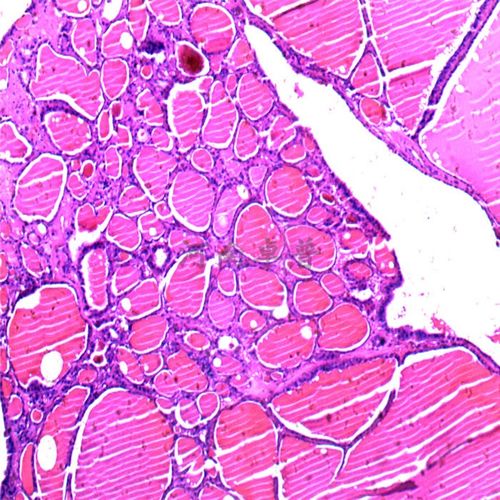

河南卓普 大学职院 医学院病理实验室专用 病理切片动脉粥样硬化